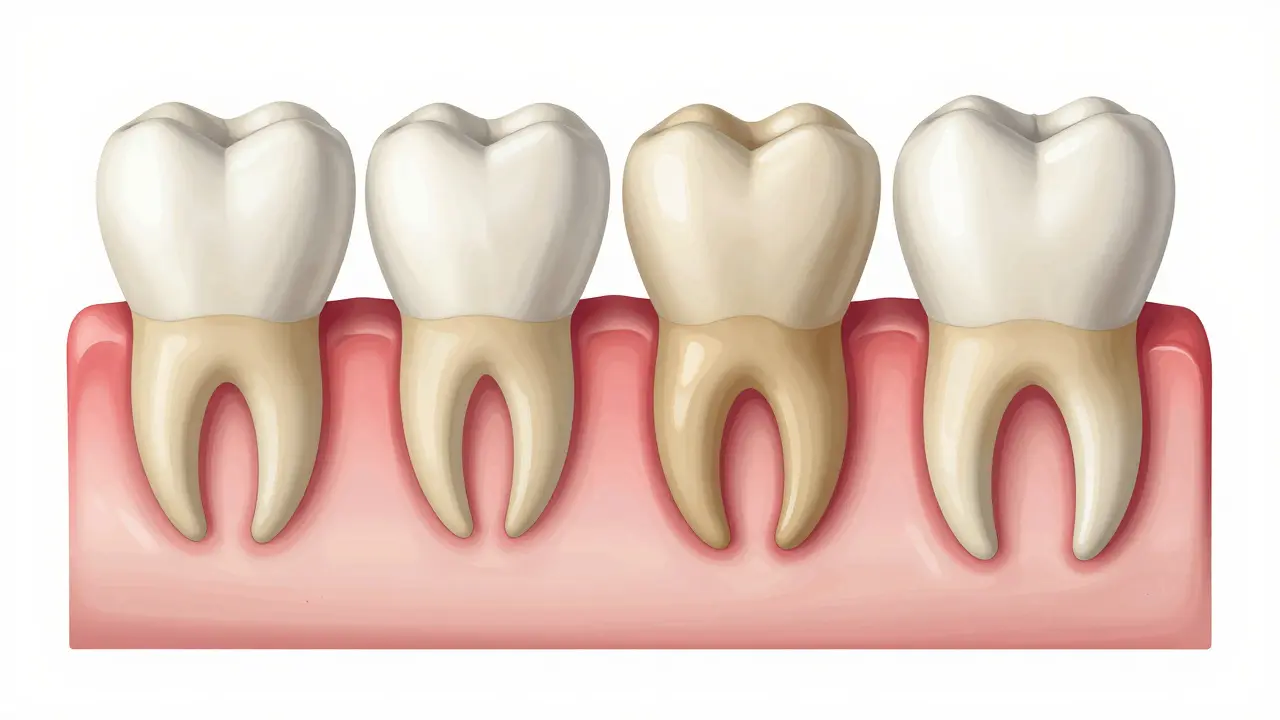

Různorodost tvarů: Ne každý zub je stejný

Možná si myslíte, že všechny kořeny vypadají stejně, ale realita je mnohem zajímavější. Tvar kořene přesně odpovídá funkci zubu. Řezáky mají za úkol krájet, zatímco k둡ky drtí. To se odráží v jejich konstrukci.

Rozdíly v počtu a tvaru kořenů podle typu zubu

Typ zubu Počet kořenů Vlastnosti tvaru Hlavní funkce

Řezáky 1 Štíhlý, mírně zpločatělý Kousání a oddělování

Klydné zuby 1 Silný, dlouhý a ostrý Trhání potravy

Premoláry 1 až 2 Střední délka, robustnější Drtvění a mletí

Molaře 2 až 3 Rozestupné, široká základna Konečné rozdrtvění potravy

Zajímavostí jsou horní první moláry, které mají typicky tři kořeny (dvě vlasti a jeden vestřední). To jim dává obrovskou stabilitu, protože rozkládají tlak při žvýkání do větší plochy kosti. Naopak dolní řezáky mají kořeny velmi úzké, protože nemusí znášet tak velké přetlaky jako zadní zuby.

Srovnání různých tvarů a počtů kořenů u řezáků, klyků, premolárů a molárů.